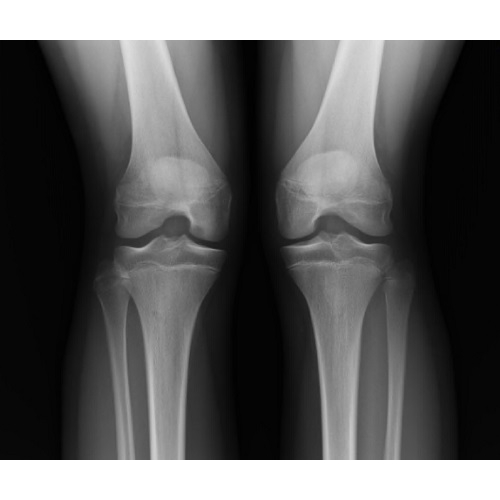

She noted three years of medial knee pain without mechanical symptoms that had recently worsened despite no acute inciting event. X-ray noted a possible osteochondritis dissecans (OCD) lesion of the distal medial right femoral condyle Case Photo #1 Case Photo #2 . MRI showed 9 x 7 mm osteochondritis dissecans (OCD) of the same location Case Photo #3 Case Photo #4 . She was instructed to discontinue impact exercises such as running and equestrian. She was permitted to cross train and was fitted in a hinged knee brace. At three month follow up, she was having minimal pain with the permitted activities and OCD lesion was healing well on x-ray Case Photo #5 Case Photo #6 . She was released to start graded return to activity, including running and equestrian. However, at one month follow up, she was experiencing persistent knee pain without effusion and new mechanical symptoms.